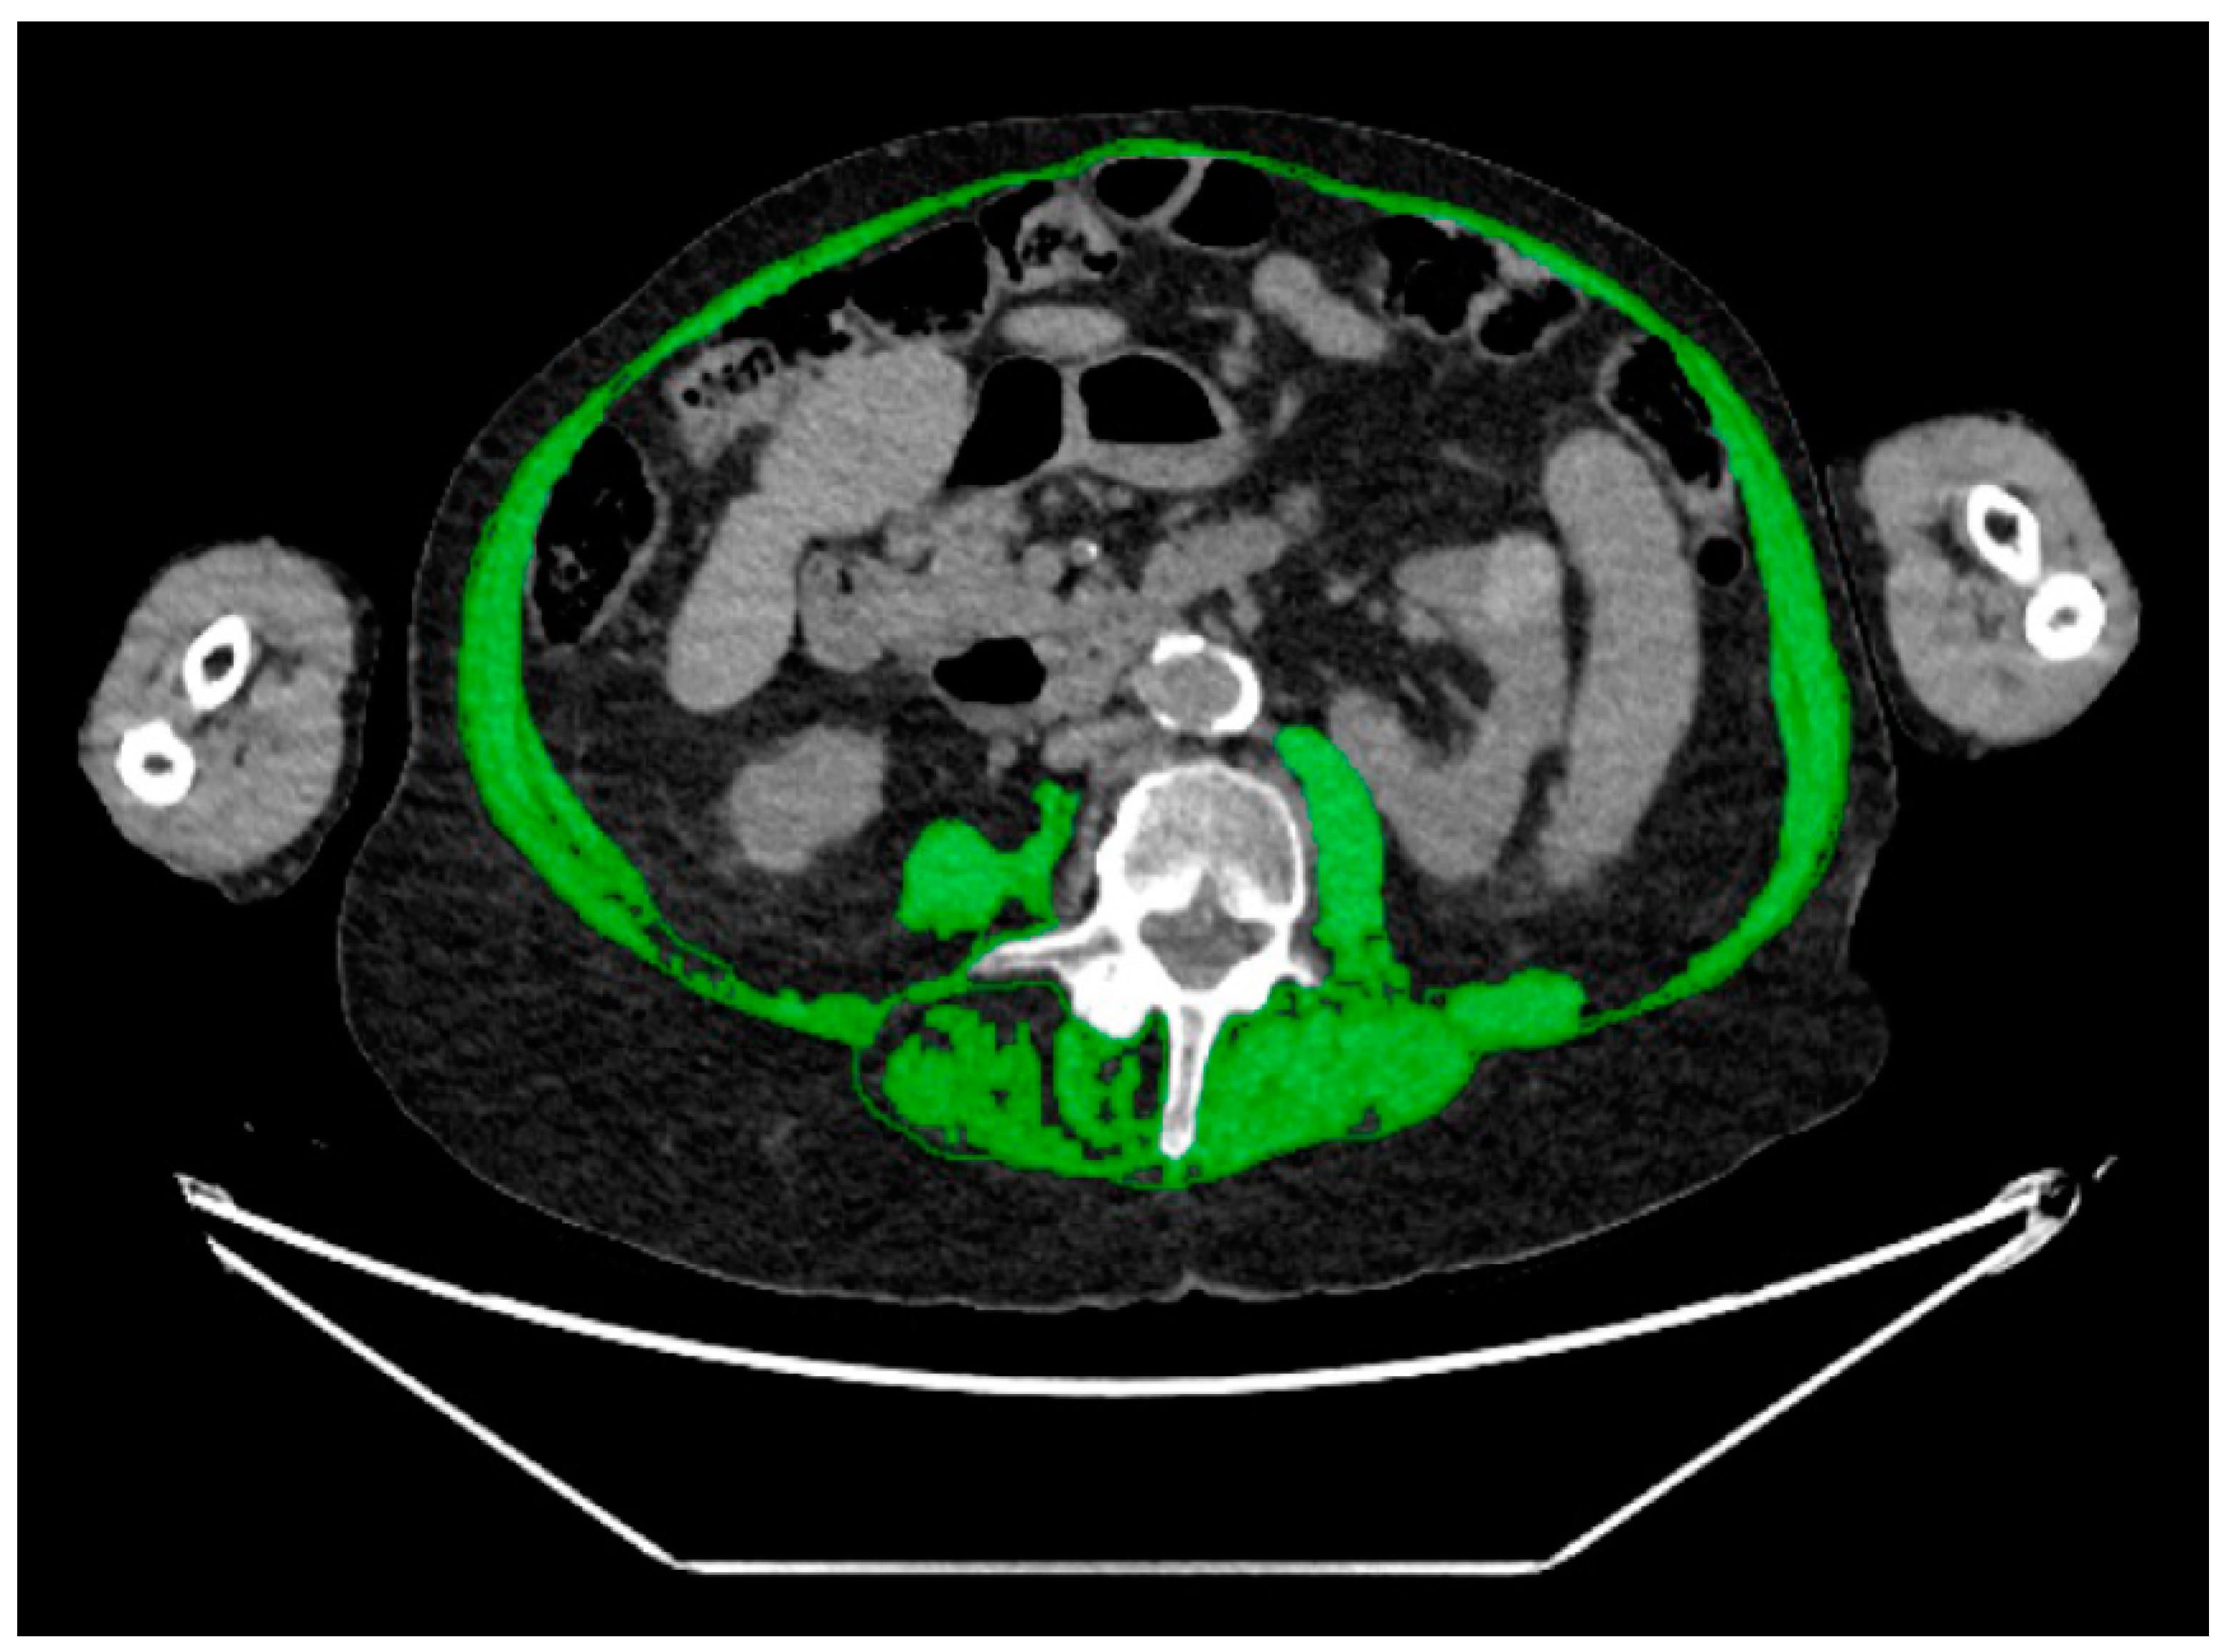

2.3. CT Body Composition Assessment

| Body composition measures a | Median (IQR) or % (n) |

| Muscle | |

| Area (cm2) | 140 (116–165) |

| Muscle area (cm2) | 0.99 (0.98; 0.99) | 0.006 | 0.047 |